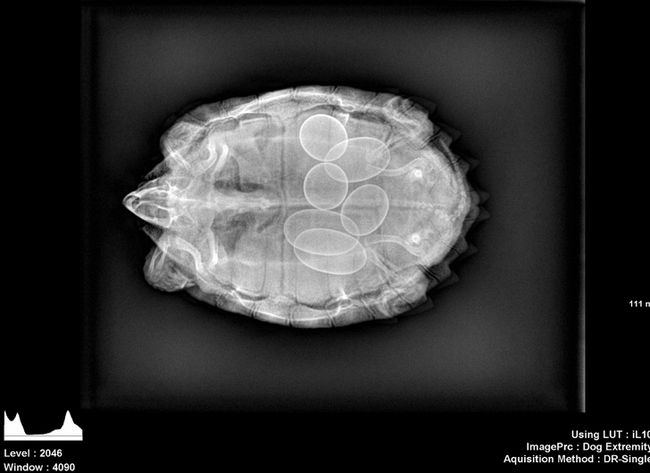

10 – Tartaruga gestante